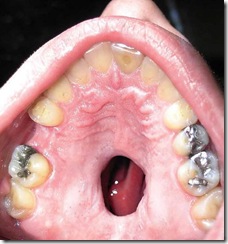

A cocaína pode provocar hemorragias nasais, os alimentos passam da boca para as narinas) e alguns outros efeitos desastrosos também podem ocorrer numa situação como essa apresentada na imagem ao lado.

O caso de um jovem americano de 25 anos vai além. Ele foi para o hospital com um buraco no palato, um resultado da morte do tecido causadas pelo consumo de cocaína.